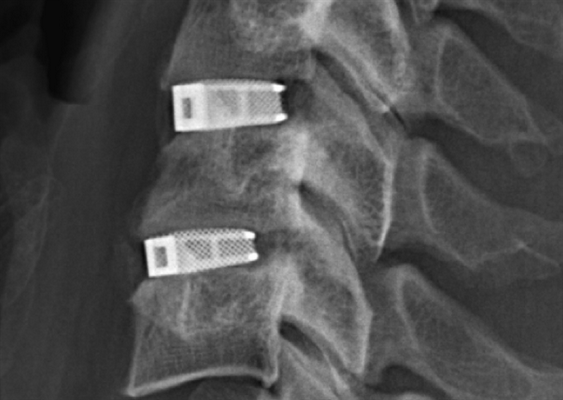

Кейджы межпозвоночных дисков поясничного отдела.

В преобладающем количестве подобные операции заключаются в достижении полного обездвиживания патологических уровней за счет прочного скрепления двух или более позвонков ригидными конструкциями. Это позволяет позвонкам с течением некоторого времени (от 3 до 6 месяцев) срастись между собой и образовать единый неподвижный костный блок. То есть, на прооперированном поле подвижность между позвонками будет заблокирована, а человек сможет нормально двигаться и ходить, не испытывая при этом боли и прочих неврологических расстройств.

Если выполняется одноуровневая фиксация, искусственно созданная обездвиженность будет неощутимой. При многоуровневой технике стабилизации, что требуется не так уж и часто, позвоночник в определенных местах утратит гибкость, из-за чего некоторые элементы движений станут выполняться несколько в ограниченной амплитуде.